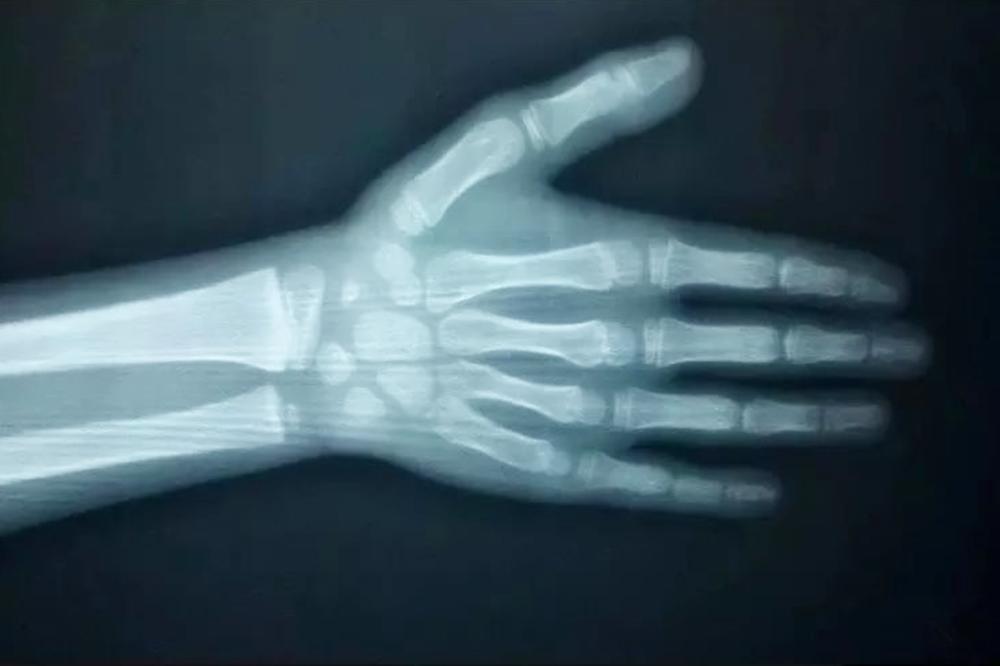

孩子身高能长到什么程度,往往取决于最后骨骼线的闭合时间 。骨骼线闭合得早,自然身高不再生长,最后身高定型;而骨骼线闭合得晚,身高便仍然有增长的机会。

正常情况下,骨龄应该是和孩子的实际年龄相符合,但骨骼的发育也会受到饮食营养、睡眠、运动等多种因素的影响,因此骨龄更多时候会和实际年龄出现偏差,出现骨龄提前或者落后等情况。